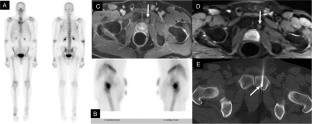

Staging patients with high-risk prostate cancer (HRPCa) with conventional imaging of computed tomography (CT) and bone scintigraphy (BS) is suboptimal. Therefore, we aimed to compare the accuracy of whole-body magnetic resonance imaging (WBMRI) with conventional imaging to stage patients with HRPCa.

Among 92 patients enrolled, 15 (16.3%) and 8 (8.7%) patients were found to have lymphatic and bone metastases, respectively. The sensitivity, specificity, and accuracy of WBMRI in detecting lymphatic metastases were 0.60 (95% confidence interval 0.32–0.84), 0.84 (0.74–0.92), and 0.80 (0.71–0.88), respectively, while CT were 0.20 (0.04–0.48), 0.92 (0.84–0.97), and 0.80 (0.71–0.88). The sensitivity, specificity, and accuracy of WBMRI to detect bone metastases were 0.25 (0.03–0.65), 0.94 (0.87–0.98), and 0.88 (0.80–0.94), respectively, while CT and BS were 0.12 (0–0.53), 0.94 (0.87–0.98), and 0.87 (0.78–0.93). For evaluating lymphatic metastases, WBMRI demonstrated a higher sensitivity (p = 0.031) and discrimination compared to CT (0.72 versus 0.56, p = 0.019).

For staging patients with HRPCa, WBMRI outperforms CT in the detection of lymphatic metastases and performs as well as CT and BS in the detection of bone metastases. Further studies are needed to assess the cost effectiveness of WBMRI and the utility of combined PSMA PET and WBMRI.